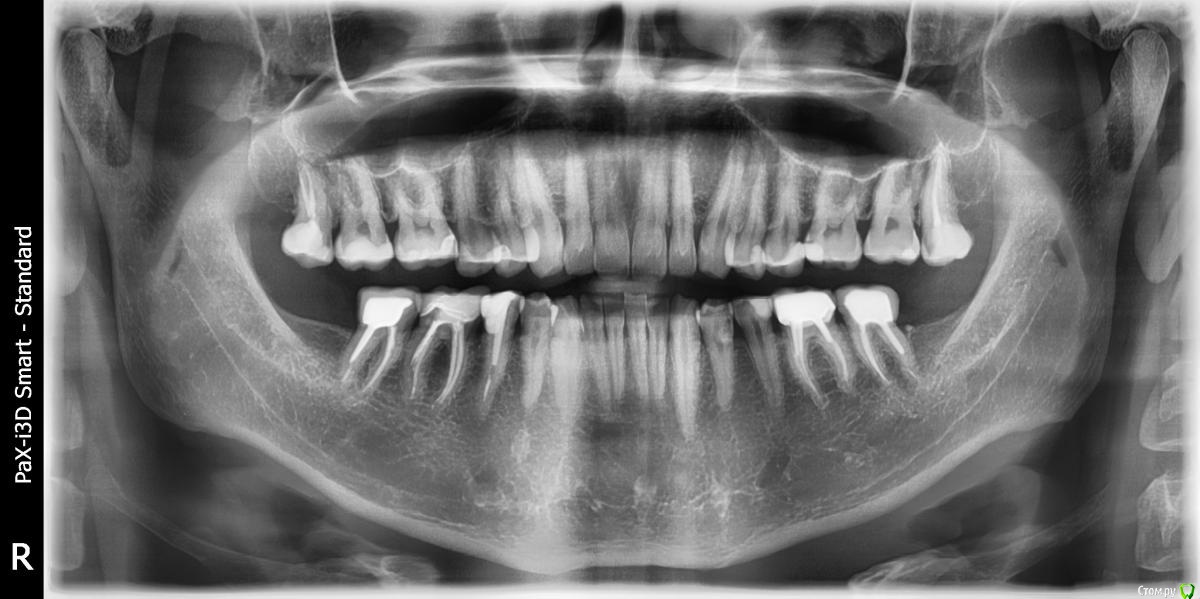

Zemtsov.alexander Опубликовано 23 октября, 2019 Автор Поделиться Опубликовано 23 октября, 2019 Спустя два месяца пациент пришёл на осмотр, есть лёгкая реакция на перкуссию. Судя по снимку есть воспаление на 45 зубе, но реагирует именно 46 Ссылка на комментарий

Zemtsov.alexander Опубликовано 23 октября, 2019 Автор Поделиться Опубликовано 23 октября, 2019 Вот панорамный снимок Ссылка на комментарий